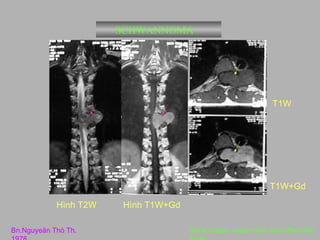

SCHWANNOMA

Hình T1W

Bn.Nguyeãn Thò Th.

Hình T2W

Hình T1W+Gd

Khoa Chaån ñoaùn hình aûnh /Bv Chôï

T1W

T1W+Gd